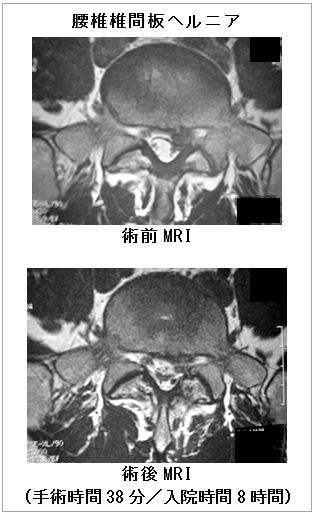

このMEDよりさらに進化し、より侵襲の少ない手術として近年注目されているのがPELD(Percutaneous Endoscopic Lumber Discectomy:経皮的内視鏡下腰椎椎間板摘出術)であり、通称「ペルド」と呼ばれています。

2.早期の社会復帰が可能

日帰りで手術ができます。術後の注意点は特にありません。経過は患者さんによって異なりますが、術後に痛みがなくなれば、すぐに動けるようになります。術後に安静にしているならPELDを行う意味がありません。少しでも早く仕事がしたい、社会復帰したい、スポーツがやりたい、といった患者さんが受けに来られる手術なのです。なお、スポーツに関しては、術後に痛みがなければ、少しずつ始め、症状を見ながら運動量を増やすように指導しています。